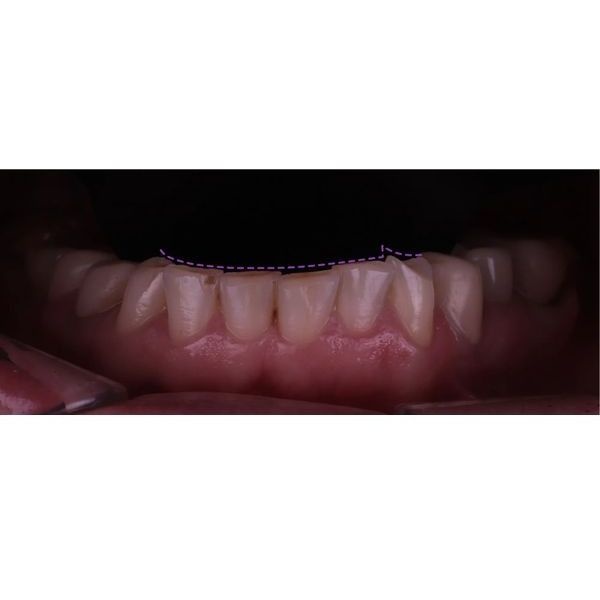

При осмотре выяснилось, что конструкции на центральных зубах хоть и выглядели эстетично, на них появились трещины и сколы, было нарушено краевое прилегание. Кроме того, у женщины наблюдалась стираемость зубов, особенно заметно стёрся нижний клык (зуб 3.3). На других зубах также присутствовали сколы.

Когда суставные головки приняли нормальное положение, наступил этап изготовления постоянных конструкций. Из непротезированных зубов у пациентки остались только нижние 4 резца и 2 клыка.

Так как женщина хотела самые тонкие виниры с минимальной обработкой, ей установили ультраниры. Из-за поднятия прикуса и значительной стёртости зубов серьёзного препарирования не потребовалось, достаточно было под микроскопом сгладить острые грани и обозначить границы будущей конструкции для техника. Так удалось максимально сохранить твёрдые ткани зуба.